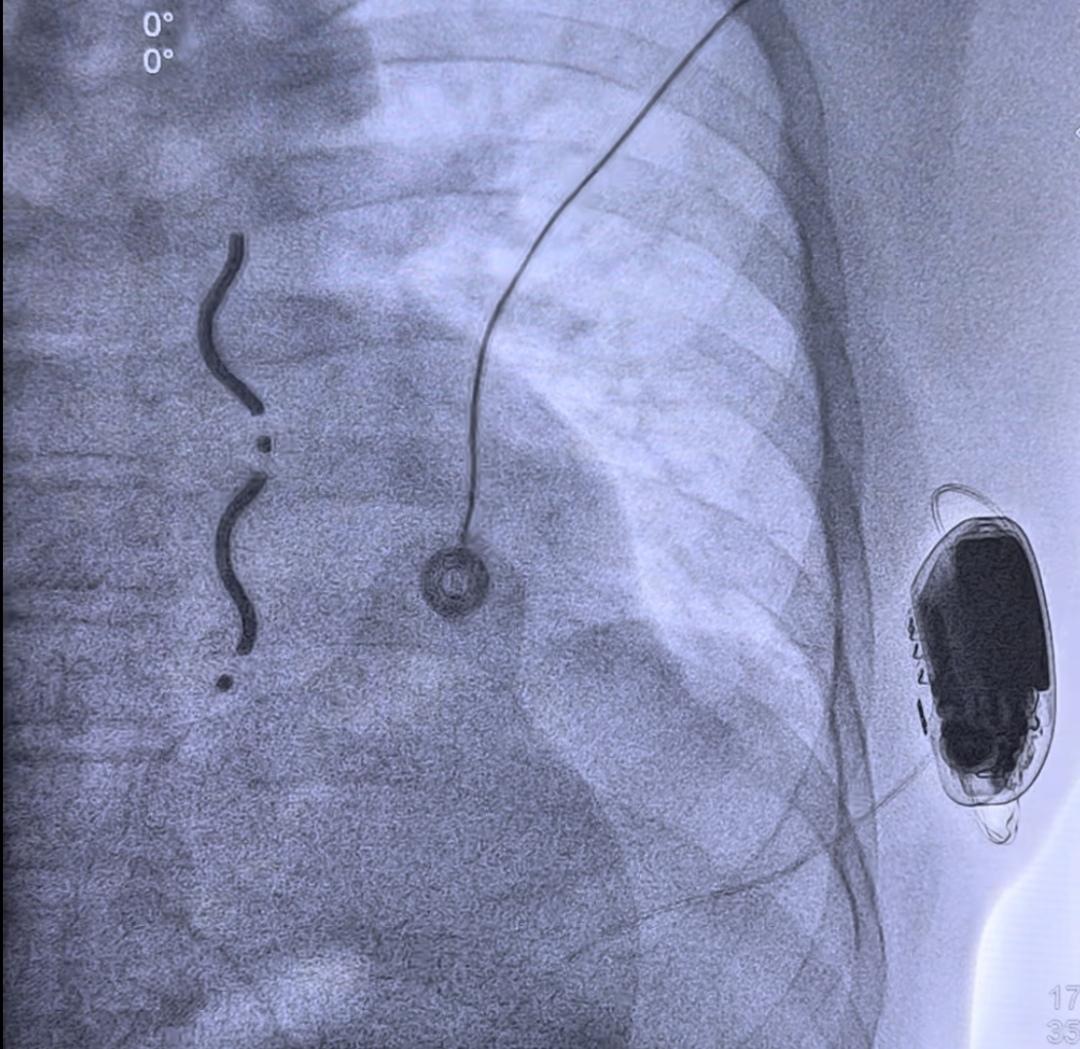

在麻醉团队和心外科团队的协助和配合下,EV-ICD植入手术顺利完成,术后患者胸骨下电极稳定,电学参数正常,除颤测试通过。患者于次日转回普通病房,优化各项参数,恢复良好。

ICD植入顺利,除颤测试成功